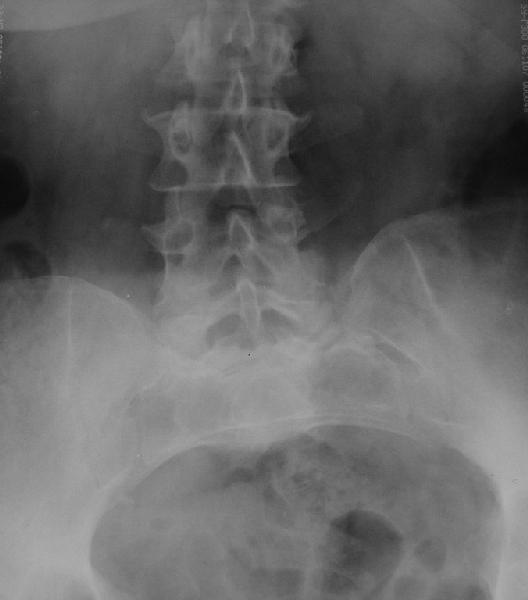

У больной 53 лет в последний год появились сильные боли в пояснице.

При обследовании выявлен анкилоз тазобедренного сустава в приведении. Видимо, в период пребывания в тяжелом состоянии появились гетеротопические оссификаты. За исключением того, что осталась одна почка, сейчас других медицинских проблем нет.

Пациентку в первую очередь беспокоят боли в спине, на отсутствие движений в суставе она вроде и не жалуется. Вопрос насчет тактики. Корсет и анальгетики вряд ли решение. Первый вариант - удаление оссификатов и эндпротезирование, второй - корригирующая остеотомия в проксимальном отделе с устранением порочного положения.

Крайне желательно выполнить МРТ поясничного отдела, так как на представленных рентгенограммах складывается впечатление о спондилолистезе L5,котрый наиболее вероятно и является причной болевого синдрома. Кроме того у болной имеется высокий риск гнойного поражения позвоночника. Только после МРТ можно планировать коррекцию вторичной деформации позвоночника.

После корригирующей остеотомии сохранится чрезмерная нагрузка на поясничный отдел за счёт анкилоза т/бедр. сустава.На фоне остеохондроза,спондилёза,спондилоартроза и спондилолистеза устранение порочного положения не избавит от болей и вряд-ли даже уменьшит их.Мне кажется тут нет альтернативы эндопротезированию.Но даже в этом случае не исключено,что позднее, на повестке появится необходимость вмешательства на позвоночнике.

Учитывая отсутствие жалоб со стороны тазобедренного сустава - оперативое лечение вряд ли принесет позитивный результат. На первый план выступает спондилолизный спондилолистез (вниматльно посмотрите снимки поясничного отдела)L5 позвонка. На наш взляд больному рекомндовано выполнить транспедикулярную коррекцию и фиксацию сегментов L4-S1 с установкой кейджа в L5-S1.